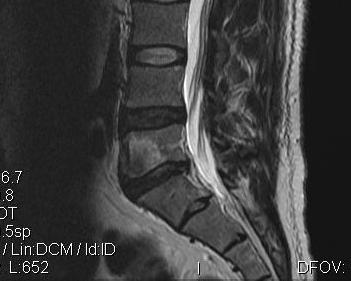

MRI

Investigation of choice

- 95% accurate

- diagnose vertebral osteomyelitis

- look for epidural abscess

Early

- T1 loss of distinction between disc and end plate

- T2 loss of normal disc intranuclear cleft

- specific for infection

Gadolinium T1

- ring enhancement